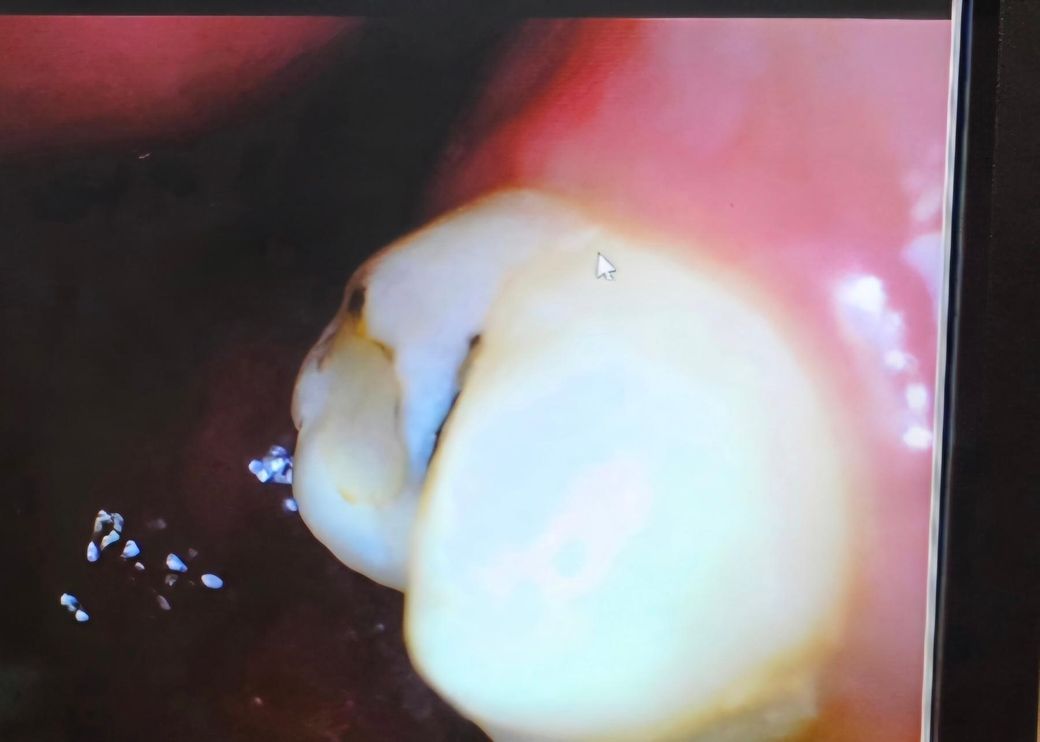

4번사진 25년10월

• 4번 째 사진

레진 착색일까요? 2차충치일까요?

레진 치료후 9개월 정도만에 주위가 까맣게 선이 생겼었거든요ㅜㅜ

이차층치보다는 착색같습니다 치과가서 그 부위 집중적으로 스케일링 한번 받아보시기 바랍니다